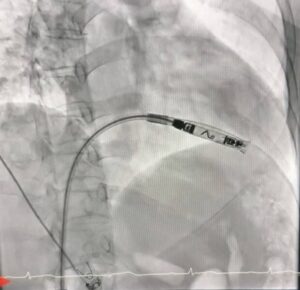

ศูนย์หัวใจ โรงพยาบาลหาดใหญ่ ประสบความสำเร็จในการรักษาผู้ป่วยโรคหัวใจเต้นช้าผิดจังหวะชนิดสมบูรณ์ (Complete Heart Block) ด้วยการใส่เครื่องกระตุ้นหัวใจชนิดไร้สาย (Leadless Pacemaker) ผ่านสายสวนหลอดเลือด ซึ่งเป็นเทคโนโลยีทางการแพทย์สมัยใหม่ และนับเป็นครั้งแรกของโรงพยาบาลในสังกัดสำนักงานปลัดกระทรวงสาธารณสุข ที่สามารถดำเนินการรักษาด้วยวิธีนี้ได้สำเร็จ

การรักษาครั้งนี้ดำเนินการโดยคณะแพทย์ผู้เชี่ยวชาญด้านการสวนหลอดเลือดหัวใจ ประกอบด้วย นพ.สริราม วิณณ์เศวต, นพ.อิทธิพล ปรีชาเวทยากุล, พญ.วรัญญา หังสพฤกษ์ พร้อมด้วยทีมพยาบาลห้องปฏิบัติการสวนหัวใจและหลอดเลือด โรงพยาบาลหาดใหญ่

ผู้ป่วยเป็นหญิงอายุ 56 ปี ได้รับการวินิจฉัยว่าเป็นโรคหัวใจเต้นช้าผิดจังหวะชนิดสมบูรณ์ (Complete Heart Block) ซึ่งจำเป็นต้องใส่เครื่องกระตุ้นหัวใจเพื่อช่วยควบคุมจังหวะการเต้นของหัวใจ โดยคณะแพทย์ได้เลือกใช้เครื่องกระตุ้นหัวใจชนิดไร้สาย (Leadless Pacemaker) ซึ่งเป็นเทคโนโลยีใหม่ล่าสุด ทำการใส่ผ่านสายสวนหลอดเลือดเข้าสู่หัวใจโดยตรง

เทคโนโลยีดังกล่าวมีข้อดีคือ ไม่มีสายไฟเชื่อมต่อกับตัวเครื่อง ลดความเสี่ยงต่อการติดเชื้อ ลดภาวะแทรกซ้อนจากสายเครื่องกระตุ้นหัวใจ และช่วยให้ผู้ป่วยฟื้นตัวได้เร็วขึ้น